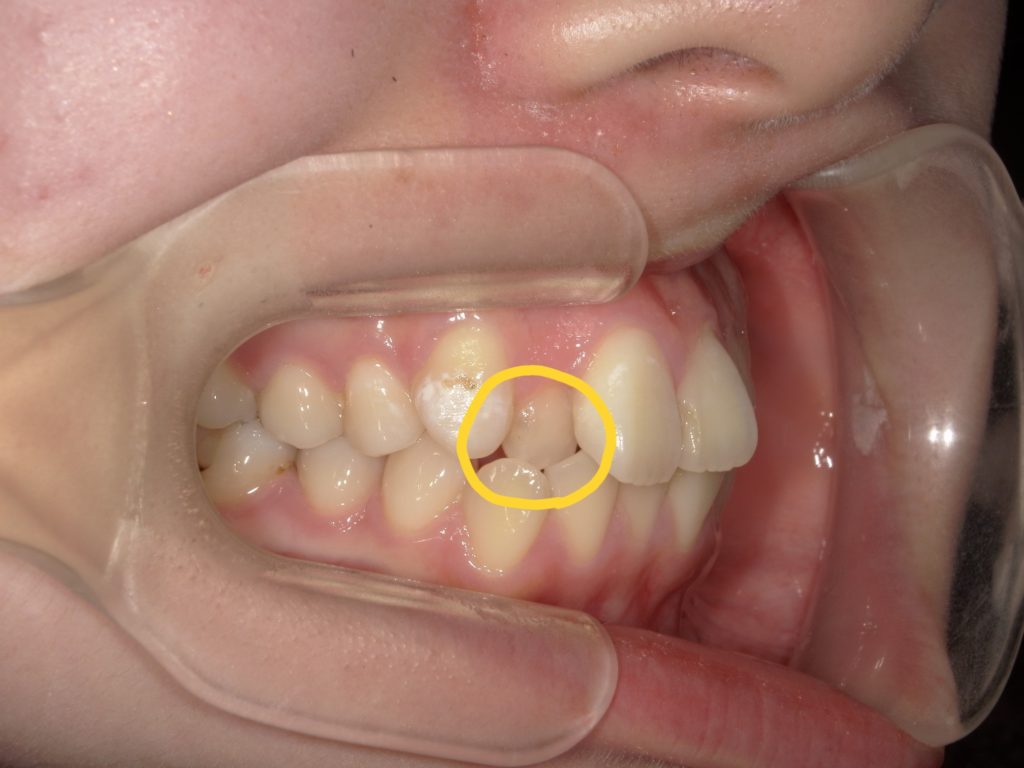

クロスバイトは要注意!

クロスバイトとは上下の歯の場所が逆になっている噛み合わせの事をいいます。写真のような歯は前に出してくる際に一時的に強く力が加わる為、他の歯よりもかなり強く揺れます。もちろん正常な噛み合わせになれば揺れも収まりますが、歯が前に出てくるまでの間は少し怖いかもしれません🥲

ただ、歯は膜と繋がっているので抜けることはありません。